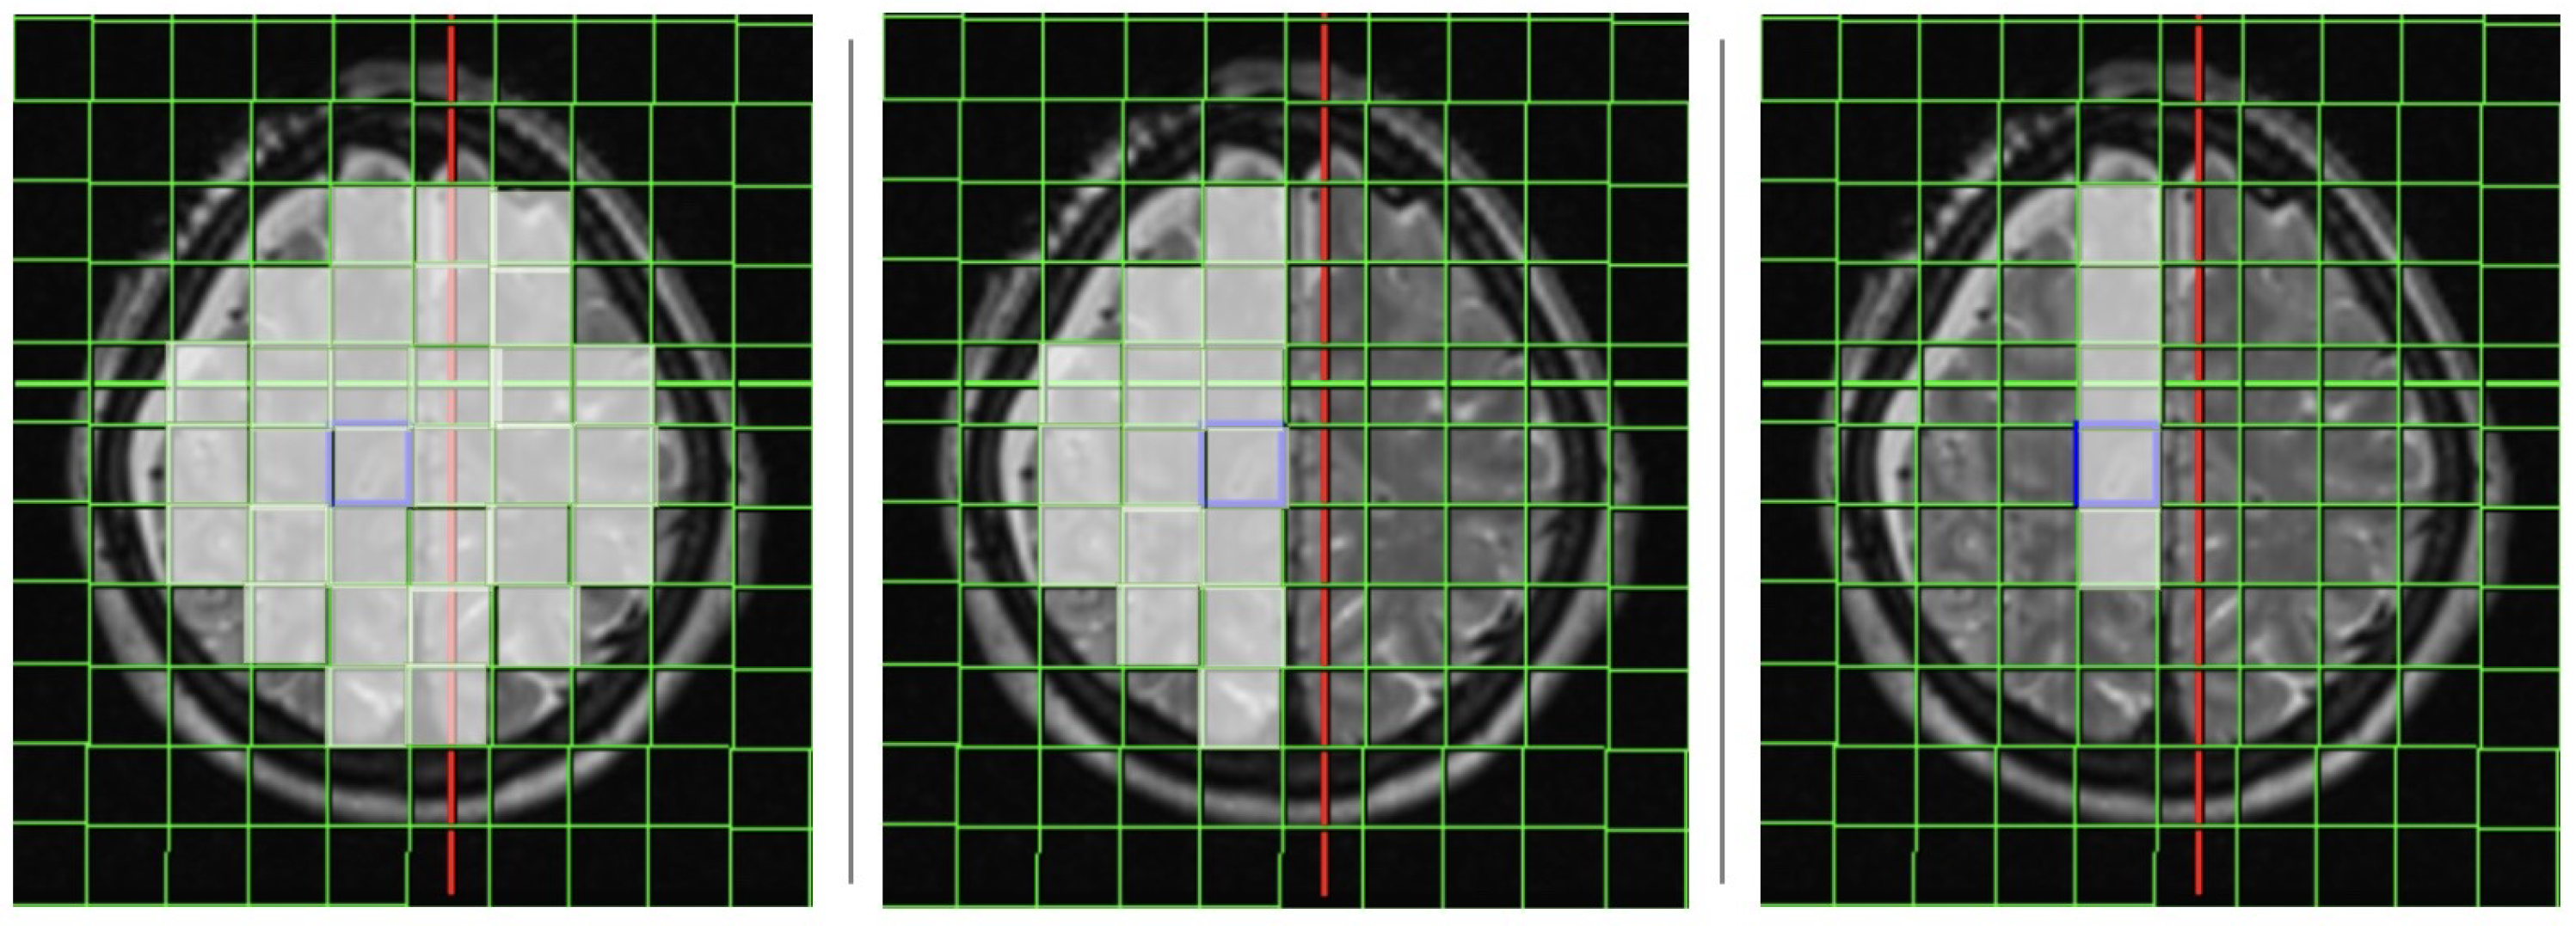

2.1. Magnetic Resonance Imaging